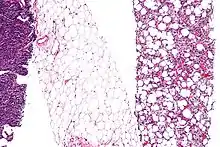

Histopathologically, ALT/WDL tumors are divided into adipocytic/lipoma-like, sclerosing, and inflammatory variants with adipocyte/lipoma-like being the most common. Adipocytic/lipoma-like ALT/WDL tumors consist of lobules of mature fat cells variably intersected with irregular fibrous septa (see the adjacent H&E stained photomicrograph). Sclerosing ALT/WDL tumors, the second most common variant, develop primarily in the retroperitoneal and paratesticular areas; it consists of scattered, atypical stromal cells within a collagenous (i.e. collagen-containing) stromal tissue background. Rare vacuole-containing lipoblasts populate this tissue. Inflammatory ALT/WDL tumors are the rarest variant. they occur most frequently in the retroperitoneum and consists of chronic inflammatory cells, e.g. lymphocytes and plasma cells plus occasional lymph node-like follicles interspersed throughout a tissue background containing fat cells.[14]

Histopathology of liposarcomas

Fig. 1 Micrograph of bone formation in a liposarcoma tumor

Fig. 2 Micrograph of a dedifferentiated liposarcoma tumor

Fig. 3 Lower-power micrograph of myxoid liposarcoma tumor

Fig. 4 Higher-power micrograph of myxoid liposarcoma tumor